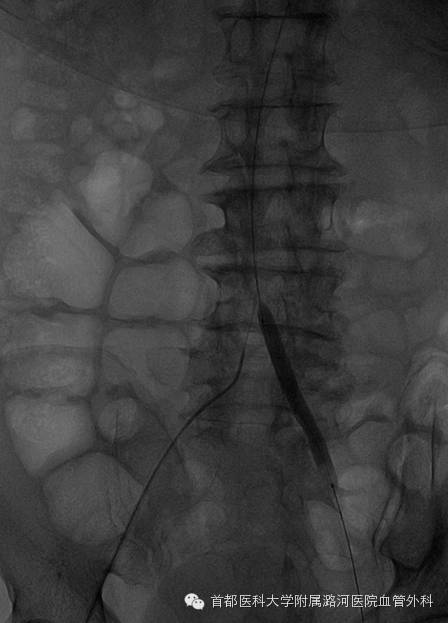

为了验证术前诊断的准确性,左侧肱动脉穿刺,腹主动脉下缘置入猪尾导管造影显示:

右侧髂总动脉起始段至髂外动脉末端全程闭塞

导丝通过右侧髂总动脉起始段受阻,其余导丝无阻力通过。

于右侧髂动脉内低压造影显示右侧髂总末端至髂外动脉全程充盈缺损。

证实右侧髂总动脉起始端重度狭窄基础上继发血栓形成;以血栓为主。

肱动脉入路超选左侧髂动脉,置入球囊阻断,预防取栓时造成对侧肢体栓塞可能